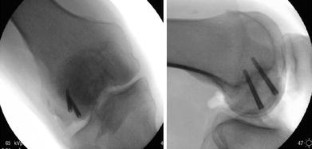

Traditional methods of fixation for Hoffa fractures have led either to the application of complicated constructs attempting to achieve stability, or to large articular surface defects created whilst countersinking headed lag screws. Both have negative implications for the patient. We describe a novel method, not previously described in the literature, using screws in a posterior to anterior direction. This provides compression perpendicular to the fracture site whilst protecting against shear and torsional forces, thereby providing more stable fixation. Furthermore, our method allows for a minimally invasive approach and uses headless compression screws, which reduces the chance of damage to the articular surface and is, therefore, less physiologically invasive.

Fig. 3